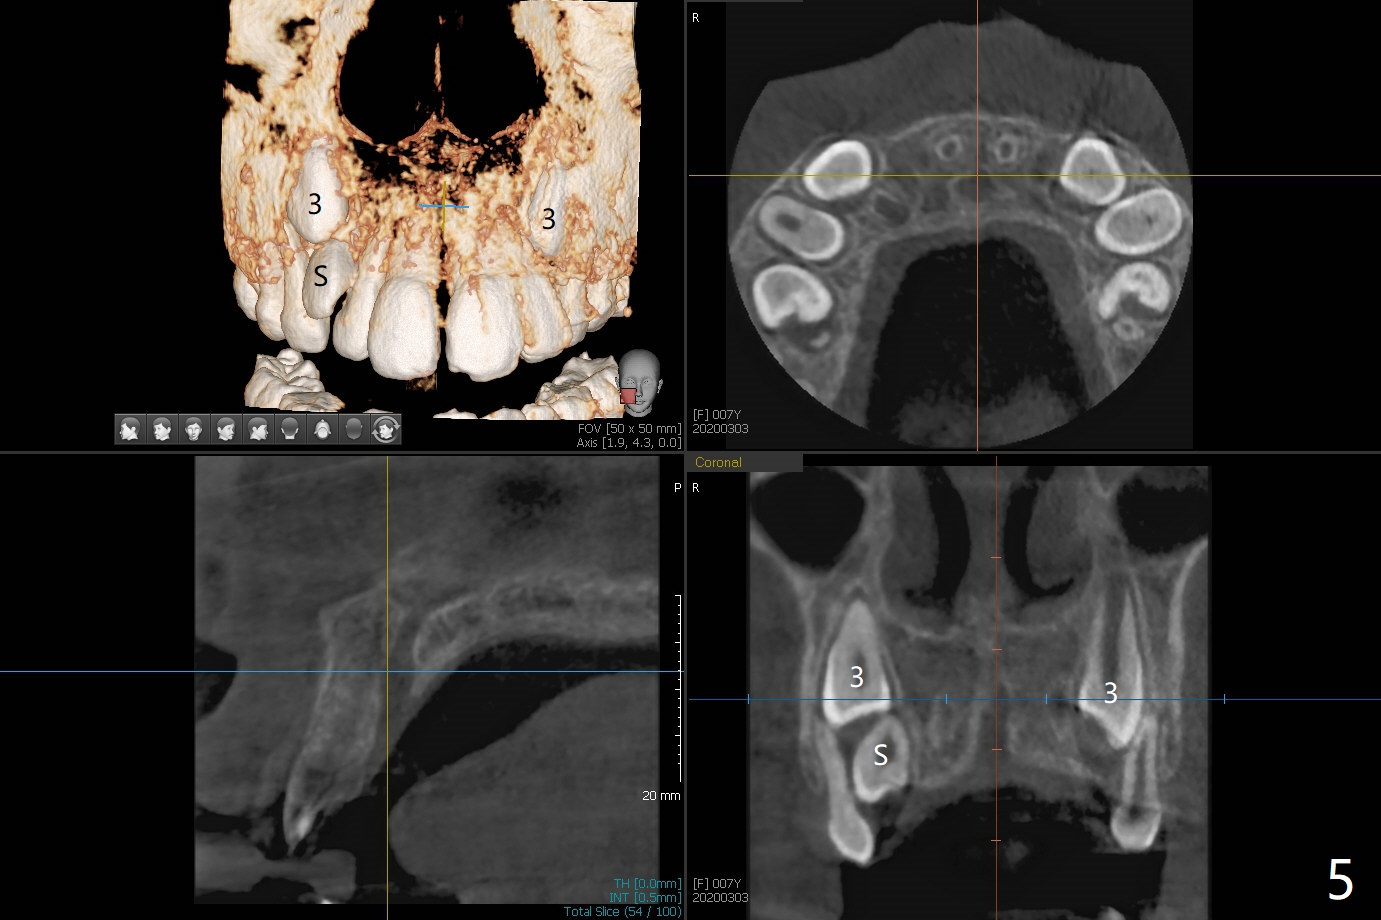

A 6-year-old woman presents to office for limited exam for caries (Fig.1). What was neglected is a super-numerary tooth (S) between UR2 and 3. One year later, the extra tooth appears to be erupting (Fig.2) and linguali-zing UR2 (Fig.3 arrow). PA shows that the extra tooth looks like a lateral (Fig.4). CT will be taken to decide which tooth needs for extrac-tion. The super-numerary tooth (S) blocks UR3 descent, as compared to that of UL3 (Fig.5). The super-numerary tooth with an abnormal cingulum (Fig.6 *) and dens in dente (Fig.6 ^) should be extracted.